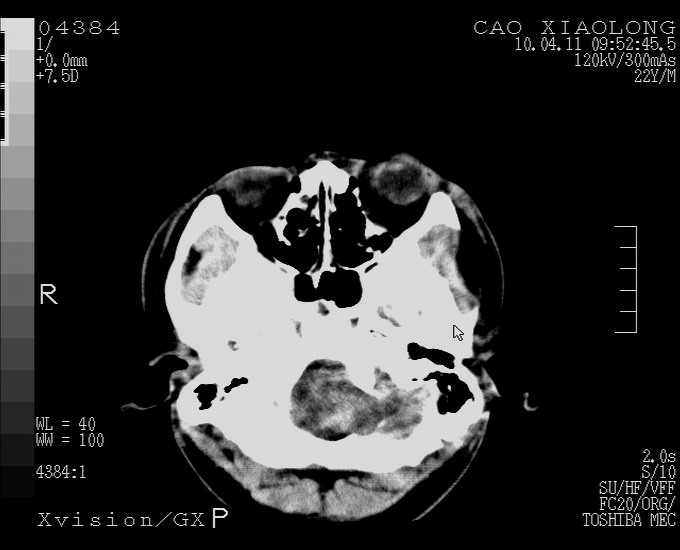

以下是引用随光逐影在2010-4-11 11:00:00的发言:[br]1)左侧额颞顶部硬膜下血肿。2)蛛网膜下腔出血。3)右侧颞顶部颅骨线形骨折。[br][br]20小时后复查:左侧额颞叶脑挫裂伤;左侧额颞顶部硬膜下血肿及蛛网膜下腔出血有吸收表现;右侧颞顶部颅骨线形骨折。[br]